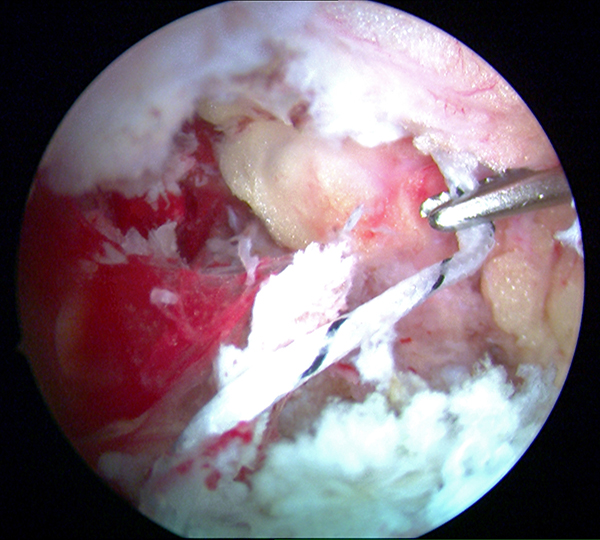

Abbildungen 5-8, Video 2

Anschließend wird die FHL-Sehne angeschlungen. Hierzu wird die Fadenschlaufe über das posteromediale Portal mit einer Fadenzange oder einem gebogenen Klemmchen um die FHL-Sehne geführt und anschließend wieder aus dem Portal herausgezogen. Nach Durchfädeln der freien Fadenenden durch die Schlaufe wird die Schlinge festangezogen. Die Technik wird in Video 2 demonstriert.

Zur Vollansicht bitte die Bilder anklicken. Fotos: M. Galla.